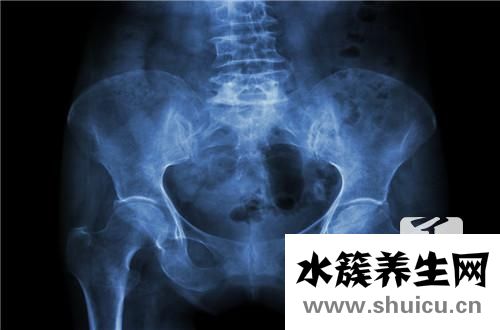

雙側(cè)骶髂關(guān)節(jié)炎是遺傳病。年齡越大越容易發(fā)展,男性患者總數(shù)遠遠高于女性患者。疾病的原因尚未確定。大部分患者臀部有疼痛,這種疼痛的抗壓強度比較高。如果生病了,可以考慮熱敷或者吃藥緩解。其次,如果比較嚴重,需要考慮醫(yī)院。醫(yī)生看了都有可能吃藥,針灸或者中醫(yī)按摩。

骶髂關(guān)節(jié)炎是關(guān)節(jié)炎中的骨關(guān)節(jié)炎的一種支系。大部分的骶髂關(guān)節(jié)炎并并不是獨立的一個病癥,只是由別的病癥造成的,如很多強直性脊椎炎炎的病人在病發(fā)前期主要表現(xiàn)為骶髂關(guān)節(jié)炎,因此 確診出骶髂關(guān)節(jié)炎還是不足的,應(yīng)進一步查驗是哪種原因造成的。

雙側(cè)骶髂關(guān)節(jié)炎關(guān)鍵的臨床癥狀主要表現(xiàn)為骶髂關(guān)節(jié)位置的疼痛病癥,尤其是在疲勞或是著涼的狀況下,疼痛會更為強烈,比較嚴重的可能會影響到一切正常活動。這就是雙側(cè)骶髂關(guān)節(jié)炎的臨床表現(xiàn)。